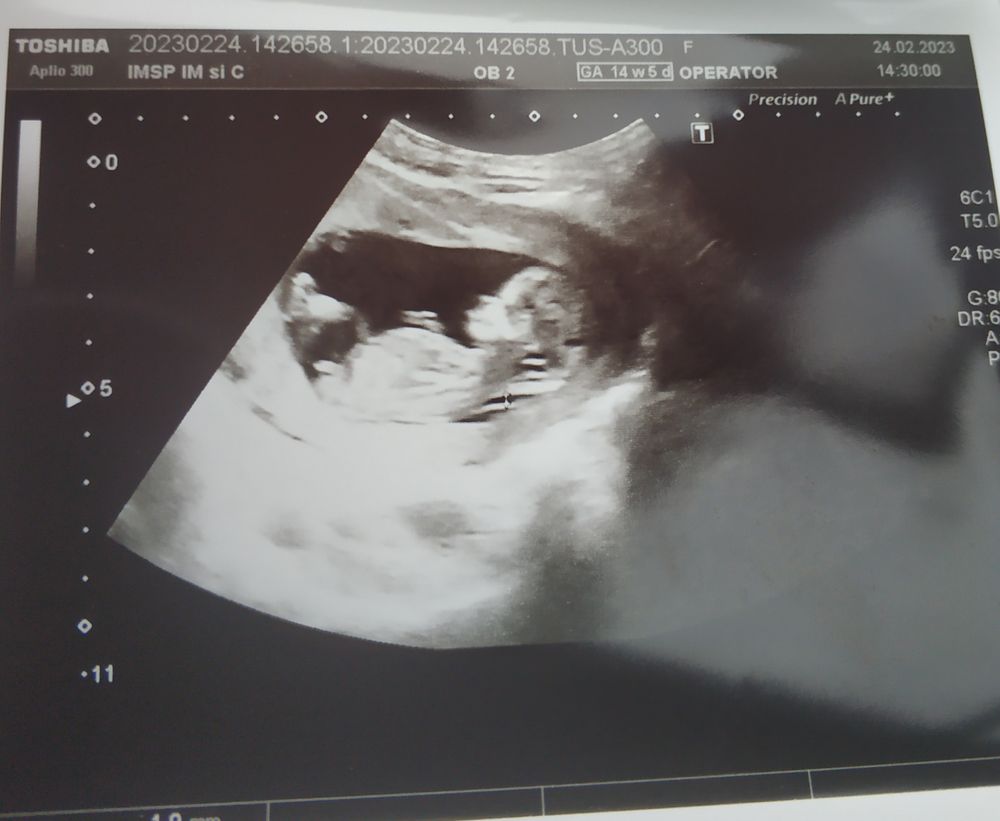

Tiana Gaidarji

Tanja, всем привет. ОЛеся простите, что вторглась сюда со своим бугорком.. Но может кто подскажет и мне.. Уж очень инетерсно. В частности вы Таитяна... Спасибо

Tanja

Tiana Gaidarji, ну вот у вас я бы сказала, что девочка. У моих так же на узи выглядело.